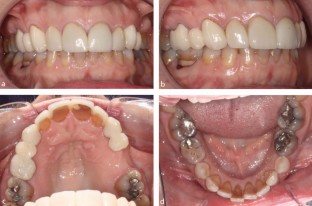

Primary molar teeth that are retained beyond their exfoliation pose a clinical decision-making challenge for dental teams. The retention of these teeth may be due to absence of a permanent successor. As a result, careful planning is required to determine if retention or extraction is necessary. This article aims to discuss the prevalence of retained primary molars, assessment and treatment planning considerations, from both orthodontic and restorative perspectives.

Explains considerations for retaining primary molars and methods of utilisation.

Laverty D P, Fairbrother K, Addison O. The Current Evidence on Retaining or Prosthodontically Replacing Retained Deciduous Teeth in the Adult Hypodontia Patient: A Systematic Review. Eur J Prosthodont Restor Dent 2018; 26: 2-15.